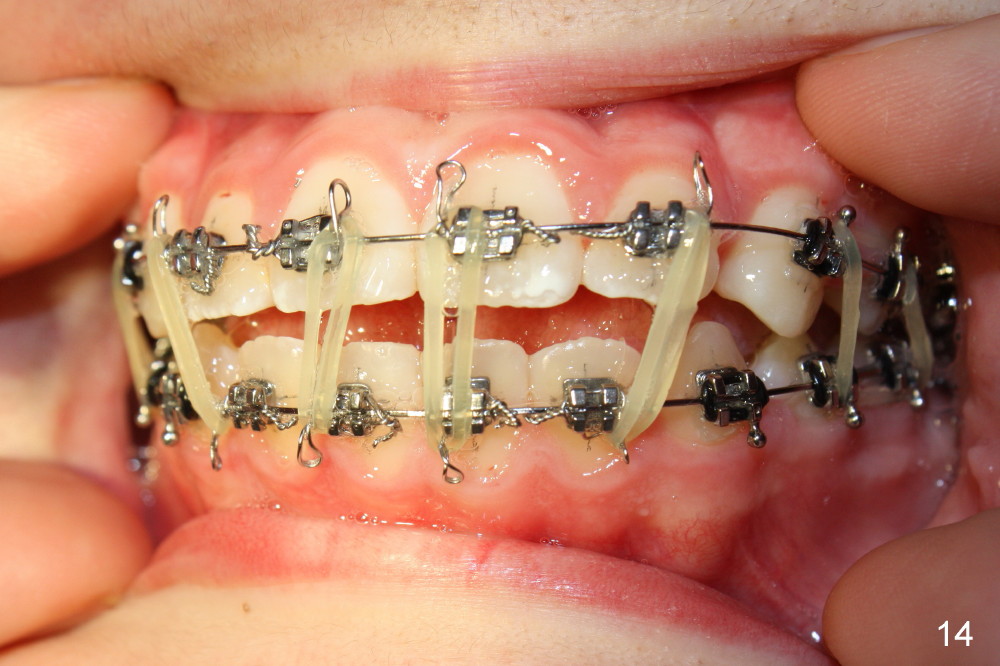

One month later, the canines has erupted completely at the expense of aggravation of anterior open bite (Fig.13,14, compare to Fig.11,12). Elastics are placed between the upper and lower incisors (Fig.14) following placement of .016' stainless steel wire for the upper arch (Fig.13).